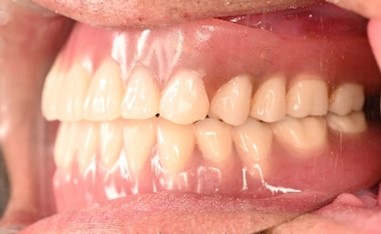

女性Kさん 60代 (マグネット式入れ歯)

2、3か所、歯が抜けた。動いている歯もある。しっかりした入れ歯をいれて、おいしく食事をしたい。

治療内容

歯周病が進行していました。下の歯3本は、保存することが出来ず、抜歯しました。残っている歯は歯周病の治療をしました。残っている上4本、下4本を利用し、総義歯タイプのマグネット式入れ歯を入れました。

所感

歯周病が進行し、残っている歯が、すべて健康な状態ではありませんでした。こういう時に残っている歯を効果的に活用できるのが、マグネット式入れ歯です。治療後「入れ歯がピタッとして動かず、何でも食べられるようになり、すごく良かったです。残っている歯を大事にして歯みがきを頑張っていきたいと思います。ありがとうございました。」と、とても喜んでくださいました。マグネット式入れ歯は、残っている歯が少なくなってきた時にとても有効な方法です。入れ歯(義歯)が、ほとんど動かないので、噛み心地も通常の総入れ歯に比べると、格段に良いです。